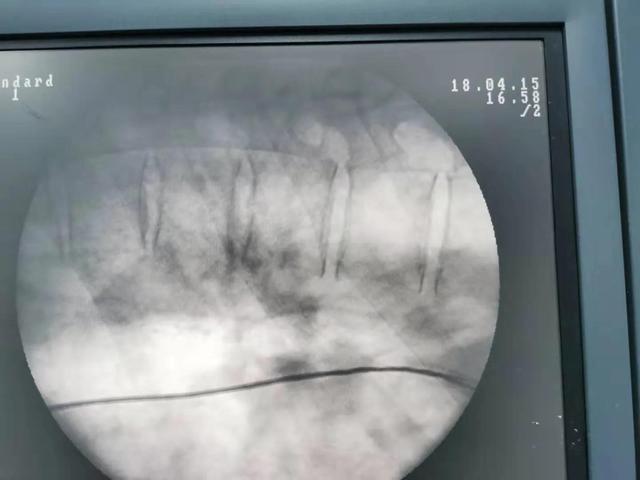

La thermocoagulation par radiofréquence utilise une aiguille de radiofréquence de 0,7 mm de diamètre, qui est ponctionnée sous guidage par arceau ou tomodensitométrie, atteint avec précision le disque malade et active la thermocoagulation. Elle s'appuie sur le rayonnement thermique pour réduire la taille du nucleus pulposus hernié et soulager la compression des racines nerveuses. La différence entre la chirurgie au plasma et la thermocoagulation par radiofréquence est que cette dernière vaporise directement le tissu du nucleus pulposus hernié.

L'incision de la chirurgie du diamètre du foramen intervertébral est petite, généralement d'environ 7 mm, sans détruire les muscles et les ligaments paravertébraux, avec moins de saignements, sans effet sur la stabilité de la colonne vertébrale, et le symptôme de la douleur est soulagé rapidement grâce à l'élimination de la compression nerveuse après l'opération. La chirurgie ouverte s'adresse aux patients présentant une hernie discale lombaire accompagnée d'une dégénérescence vertébrale lombaire, d'ostéophytes, d'une sténose spinale et d'une sténose du canal de la racine nerveuse, d'une calcification ligamentaire, ainsi qu'aux patients présentant une instabilité évidente de la colonne vertébrale lombaire.